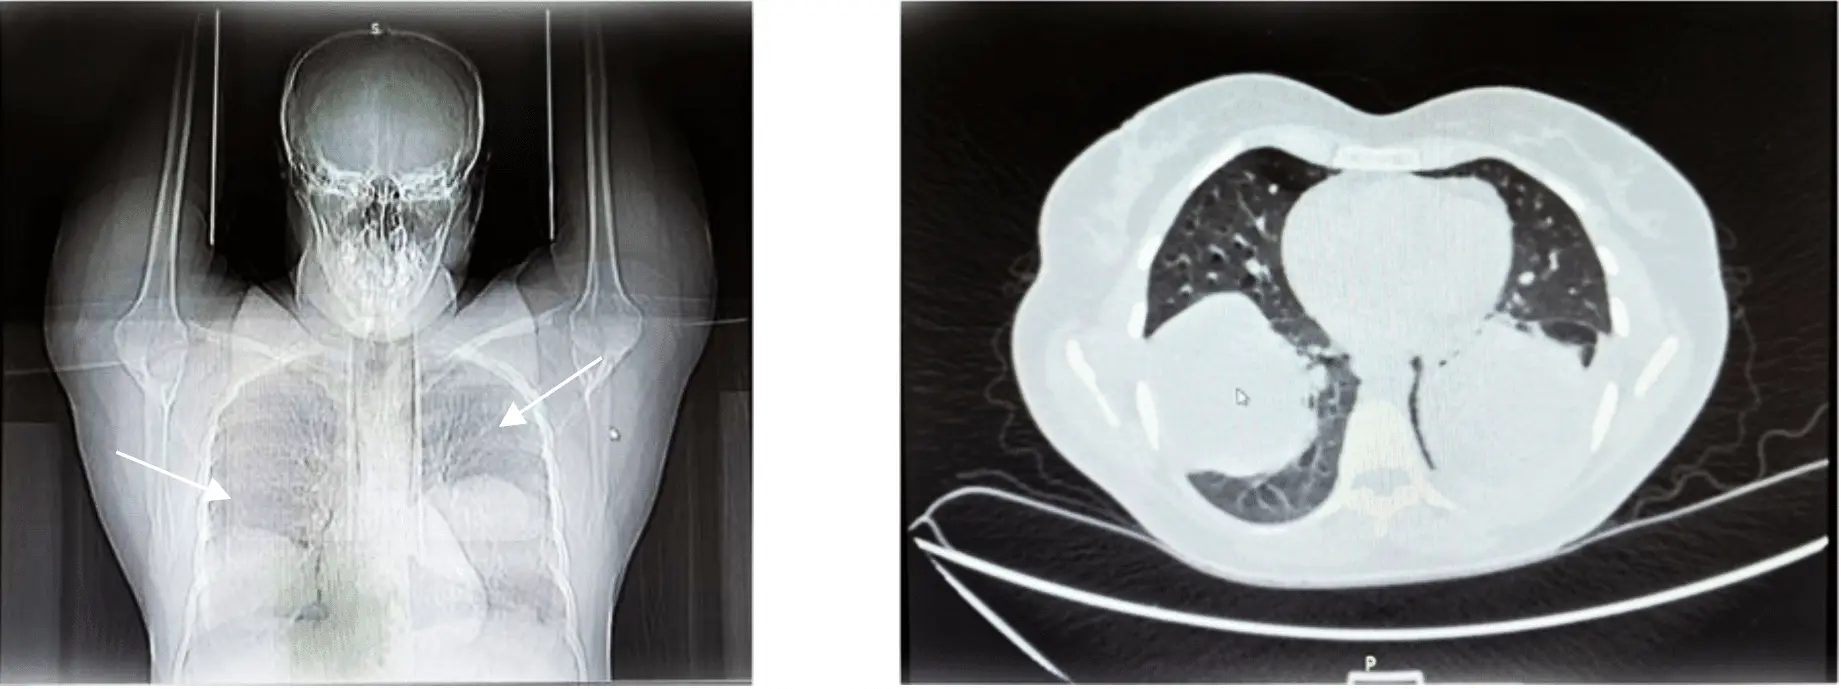

В одну из больниц Новгорода поступила женщина с рентгеновскими снимками грудной клетки. На них отчетливо просматривались крупные образования в легких, сопоставимые по размеру с яблоком: правое – 76х66х66 мм, левое – 81х69х70 мм. Пациентка, уроженка Таджикистана, долгое время занималась передержкой собак, при этом не испытывая никаких неприятных симптомов.

Микроскопический анализ подтвердил, что образования представляют собой обширные паразитарные кисты. Их причиной стал гельминт Echinococcus granulosus (эхинококк). Медики незамедлительно назначили пациентке операцию по удалению обеих кист.

Первоначально успешно провели открытую операцию по удалению левой кисты. Послеоперационный период прошел гладко, пациентку выписали с назначением антигельминтного препарата широкого действия. Удаление правой кисты запланировали через пять месяцев. Однако при подготовке к ней у женщины возник кашель с гнойной мокротой, поднялась температура и появились признаки дыхательной недостаточности.

— Рентген показал наличие воздуха и избытка жидкости в плевральной полости, заподозрили прорыв кисты, — отметила Ольга Азовцева. — Повторный анализ крови на антитела к Echinococcus granulosus IgG оказался положительным.